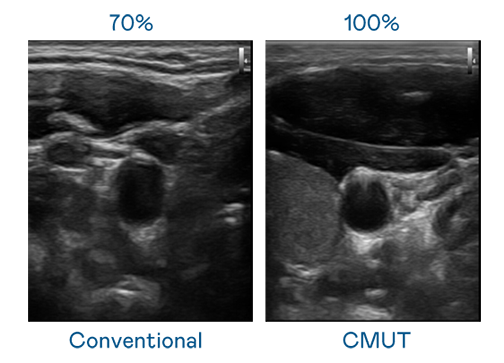

CMUT 技術是一種用電容式微機電元件來產生超音波訊號的技術。與傳統 PZT 壓電式技術相比,CMUT 頻寬增加 30%,更寬頻的超音波訊號讓影像解析度大幅提升,是實現高影像品質醫療超音波掃描、促進精準醫療發展的關鍵技術。

超音波影像的解析度高低,首先取決於探頭能發出的訊號頻寬。918搏天堂 CMUT 可提供高清晰的超音波訊號,提供高頻寬、高靈敏度、影像紋理細節更高的超音波影像,協助醫護人員縮短影像判讀時間及利用精準的醫療影像進行診斷。